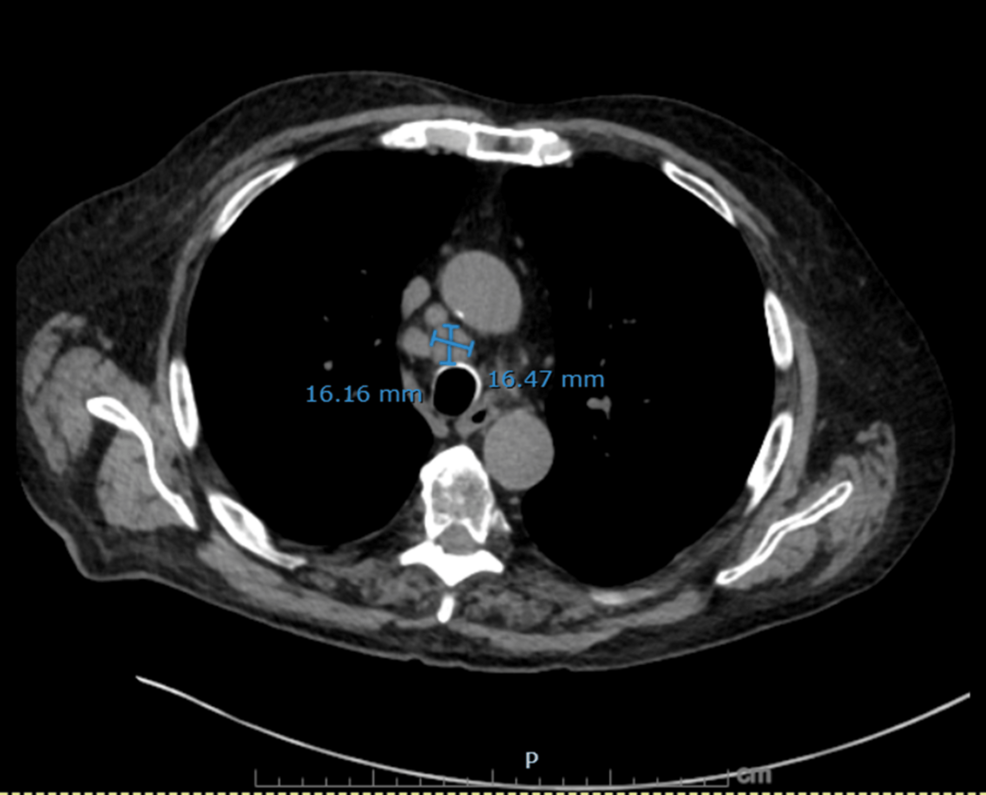

Figure 2: Non-contrast axial CT chest showing a dominant right paratracheal lymph node

A right paratracheal lymph node measuring 16.2 × 16.5 mm is demonstrated, further supporting malignant mediastinal involvement in small cell lung cancer.